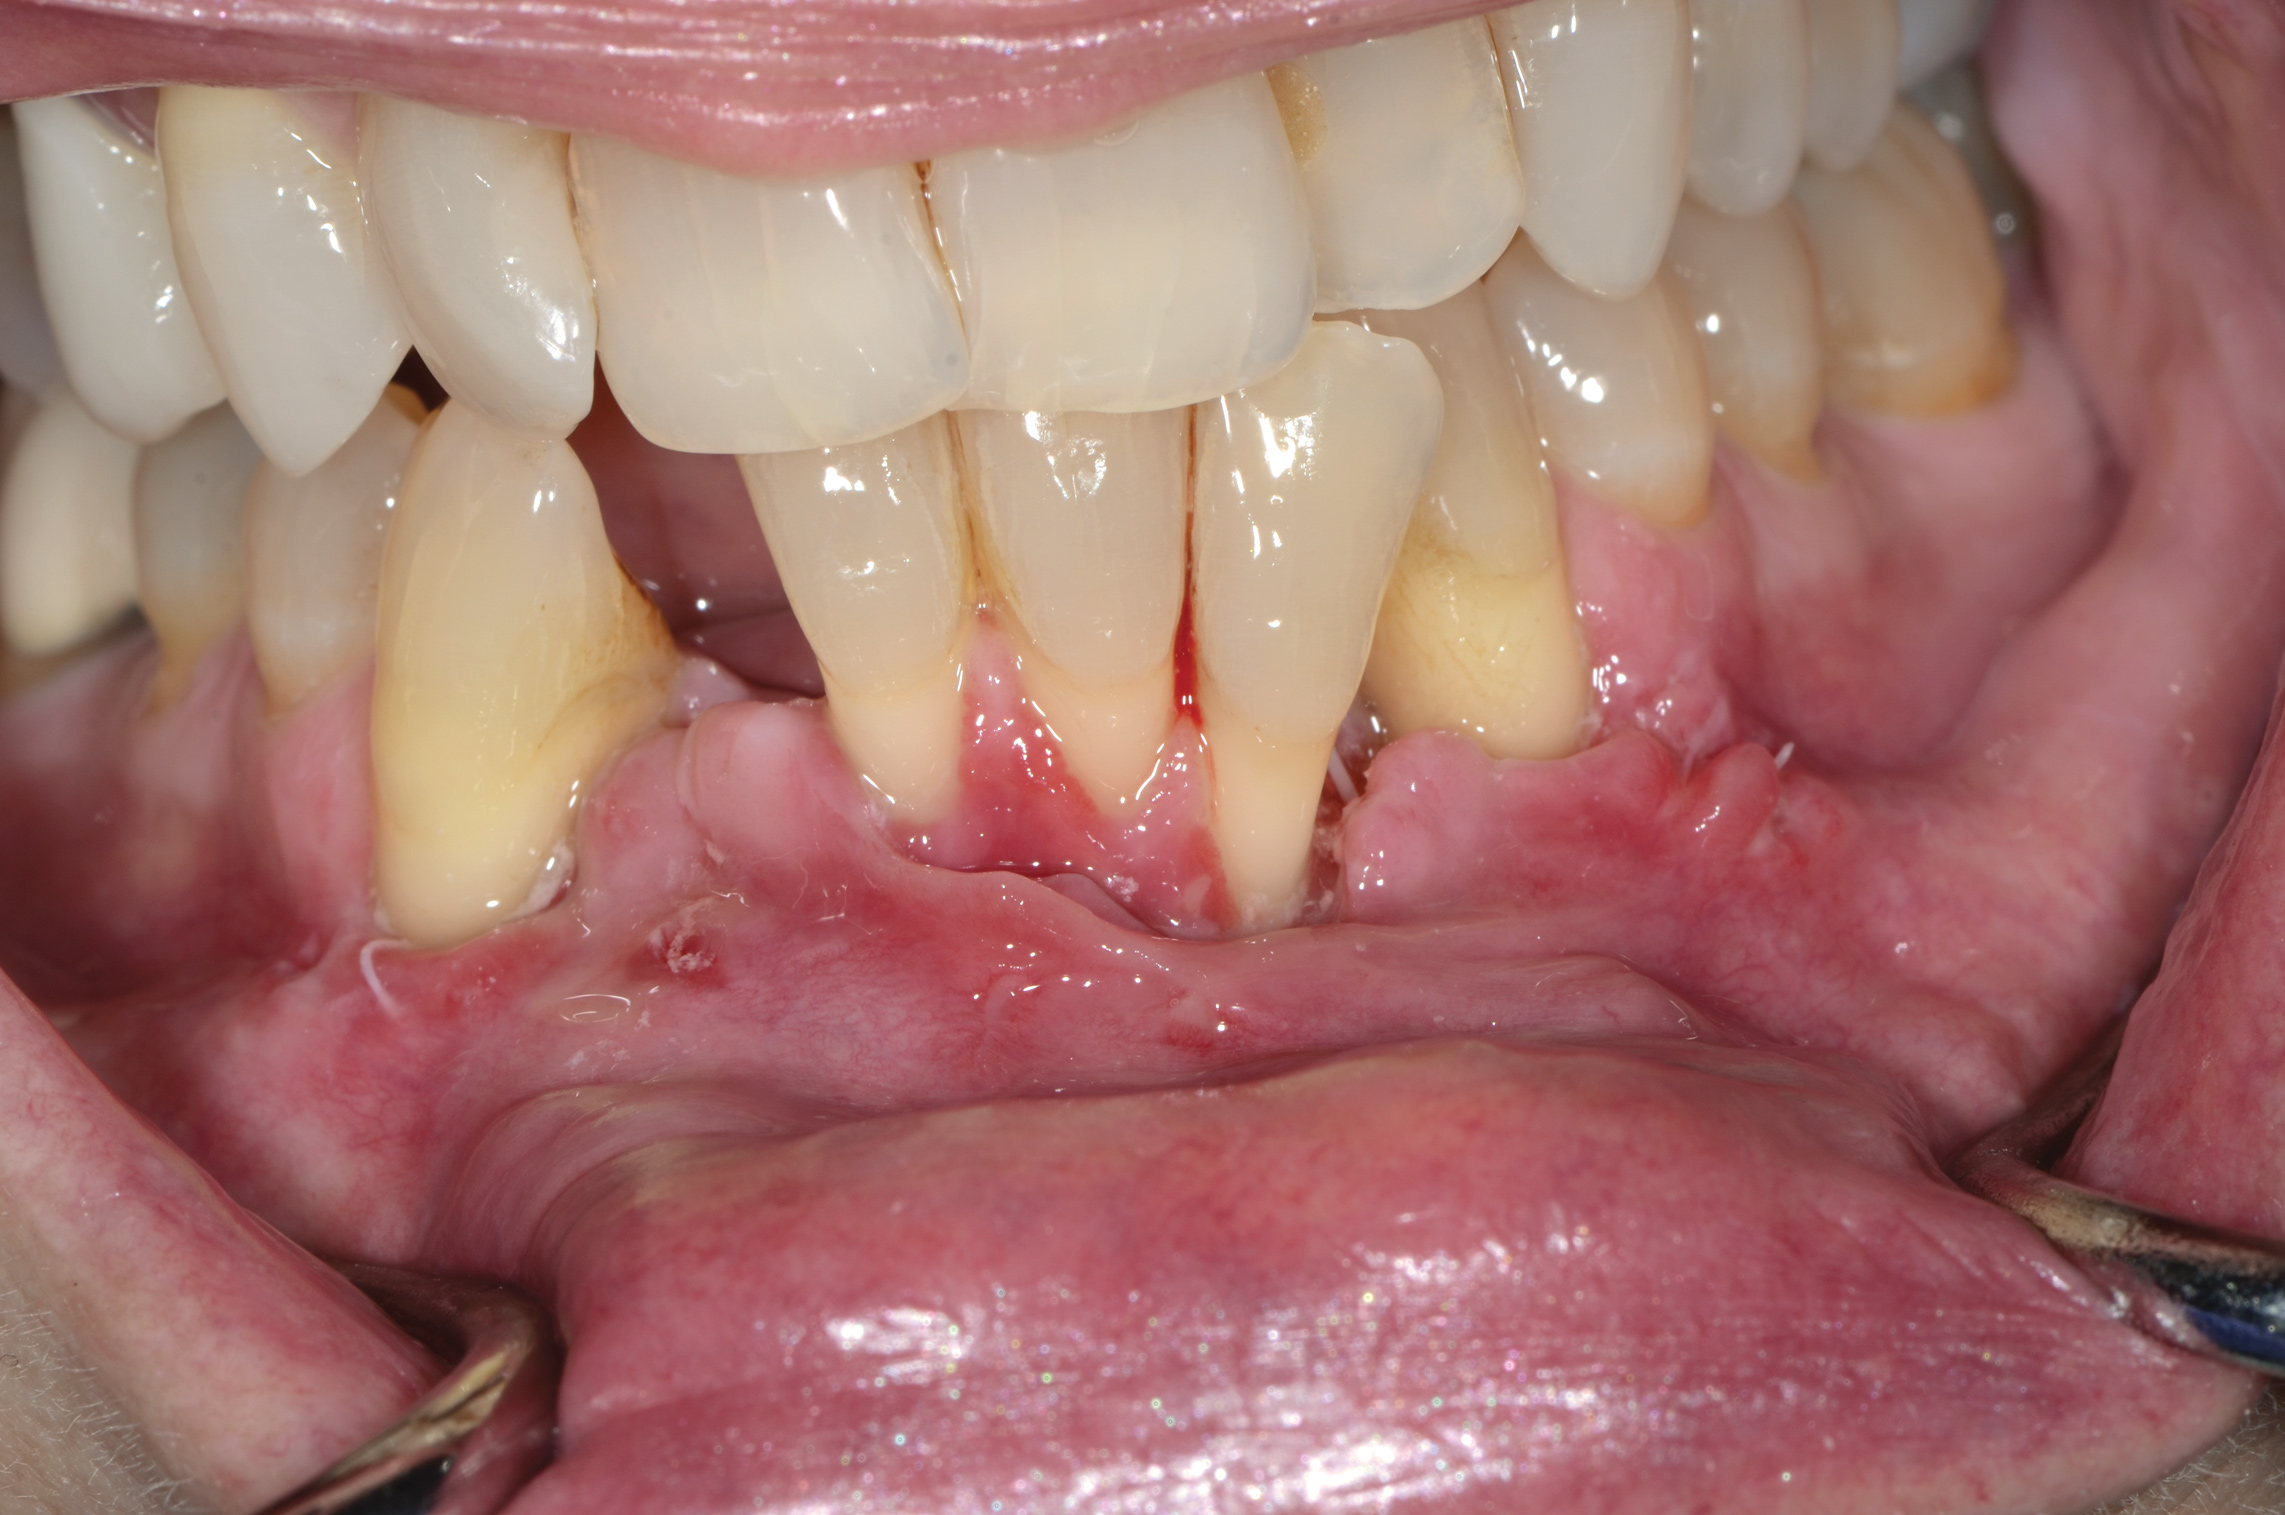

Fig 10. In this case a short vestibule was present prior to SFOT.

Figure 10

Fig 11. Suturing after SFOT procedure; note the shallow vestibule and flap tension at closure.

Figure 11

Fig 12. At 2 weeks postoperative, a flap dehiscence present on the facial was a result of the flap tension associated with the shallow vestibule.

Figure 12

Fig 13. Final outcome after SFOT; note proper alignment of teeth yet limited attached gingiva with compromised root coverage and shallow vestibule still present post-surgery.

Figure 13

Depth of Vestibule

In general, the rate of developing soft-tissue complications related to bone augmentation procedures can range from 0% to 45%.22 In the anterior mandible any regenerative procedure that requires coronal positioning and primary closure can be challenging due to several anatomical factors (Figure 10 through Figure 13). These include the mentalis muscle pull; the depth of the vestibule, which should allow for primary closure without much tension on the lip; and the thickness of tissue, which should enable the primary closure to be maintained without dehiscence that may result in bone and membrane exposure.

In compromised situations where the depth of the vestibule is shallow or a prominent muscle pull exists, several complications can occur, including suboptimal closure with excessive tension around the lower lip area; soft-tissue dehiscence and opening of flaps resulting in loss of biomaterial that may compromise bone augmentation outcome and thickness during the healing phase and tooth movement; risk of infection due to exposure of bone and membrane/acellular dermal matrix, if used; and worsening of gingival recession due to soft-tissue dehiscence and loss of thickness at grafted sites.

Possible modifications in a patient with a shallow vestibule and prominent mentalis include preliminary vestibule deepening with the use of a free gingival graft or a Botox® injection to relieve muscle pull.